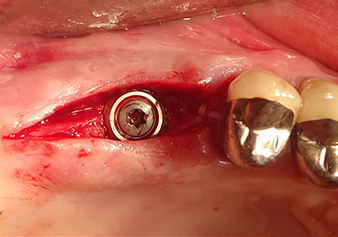

49-летняя пациентка, некурящая и не имеющая ничего примечательного в общей истории болезни, была направлена в нашу хирургическую стоматологическую клинику для хирургического удаления зуба 16 и последующей имплантации. После удаления зуба пациентка перенесла синусит в легкой форме, в результате чего мы сначала выждали шесть месяцев перед проведением операции. Остаточная высота кости при запланированном положении имплантата составляла 3-4 мм (рис. 1 и 2).

После промежуточного контроля (рис. 4) был проведен еще один этап подготовки (рис. 5). За тем, с помощью гидравлического инструмента Z35P мембрана была поднята в нужное положение (рис. 6 и 7). Далее, следовала дальнейшая пьезохирургическая подготовка ложа для имплантата, завершенная с помощью ротационного бора и лопаточной фрезы до диаметра имплантата 4,8 мм. Перед установкой имплантата под мембрану Шнейдера был введен аугментационный материал (размер частиц около 0,8-1,6 мм) (рис. 8).

Имплантация и протезирование

Для перемещения аугментационного материала в направлении верхнечелюстной пазухи атравматично, имплантат вводился очень медленно вручную (рис. 9). При этом мембрана еще раз выталкивалась в краниальном направлении. Через два месяца место операции зажило без раздражения. Через шесть месяцев рентгеновский контроль показал значительное увеличение помутнения, что свидетельствует об оссификации (рис. 10). Протезирование было проведено металлокерамической коронкой.